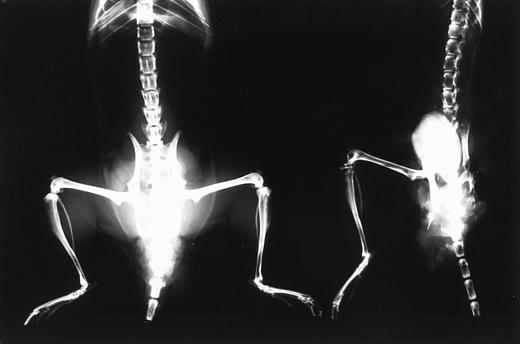

Bone resorption.Because bone resorption and extramedullary invasion of tumor cells are often induced in advanced MM, the appearance of hind leg paralysis in the mice was thought to be caused by compression of spinal cord by the tumor mass. X-ray photography showed that bone density of mice with advanced tumor growth was decreased throughout their bodies (Fig 3). Some of these mice showed obvious fractures in the femur (data not shown).

X-ray photographic observation of bones in mice 37 days after IV inoculation with KPMM2 cells. Decrease in bone density was observed in the tumor bearing mouse (right) in comparison with normal mouse (left).